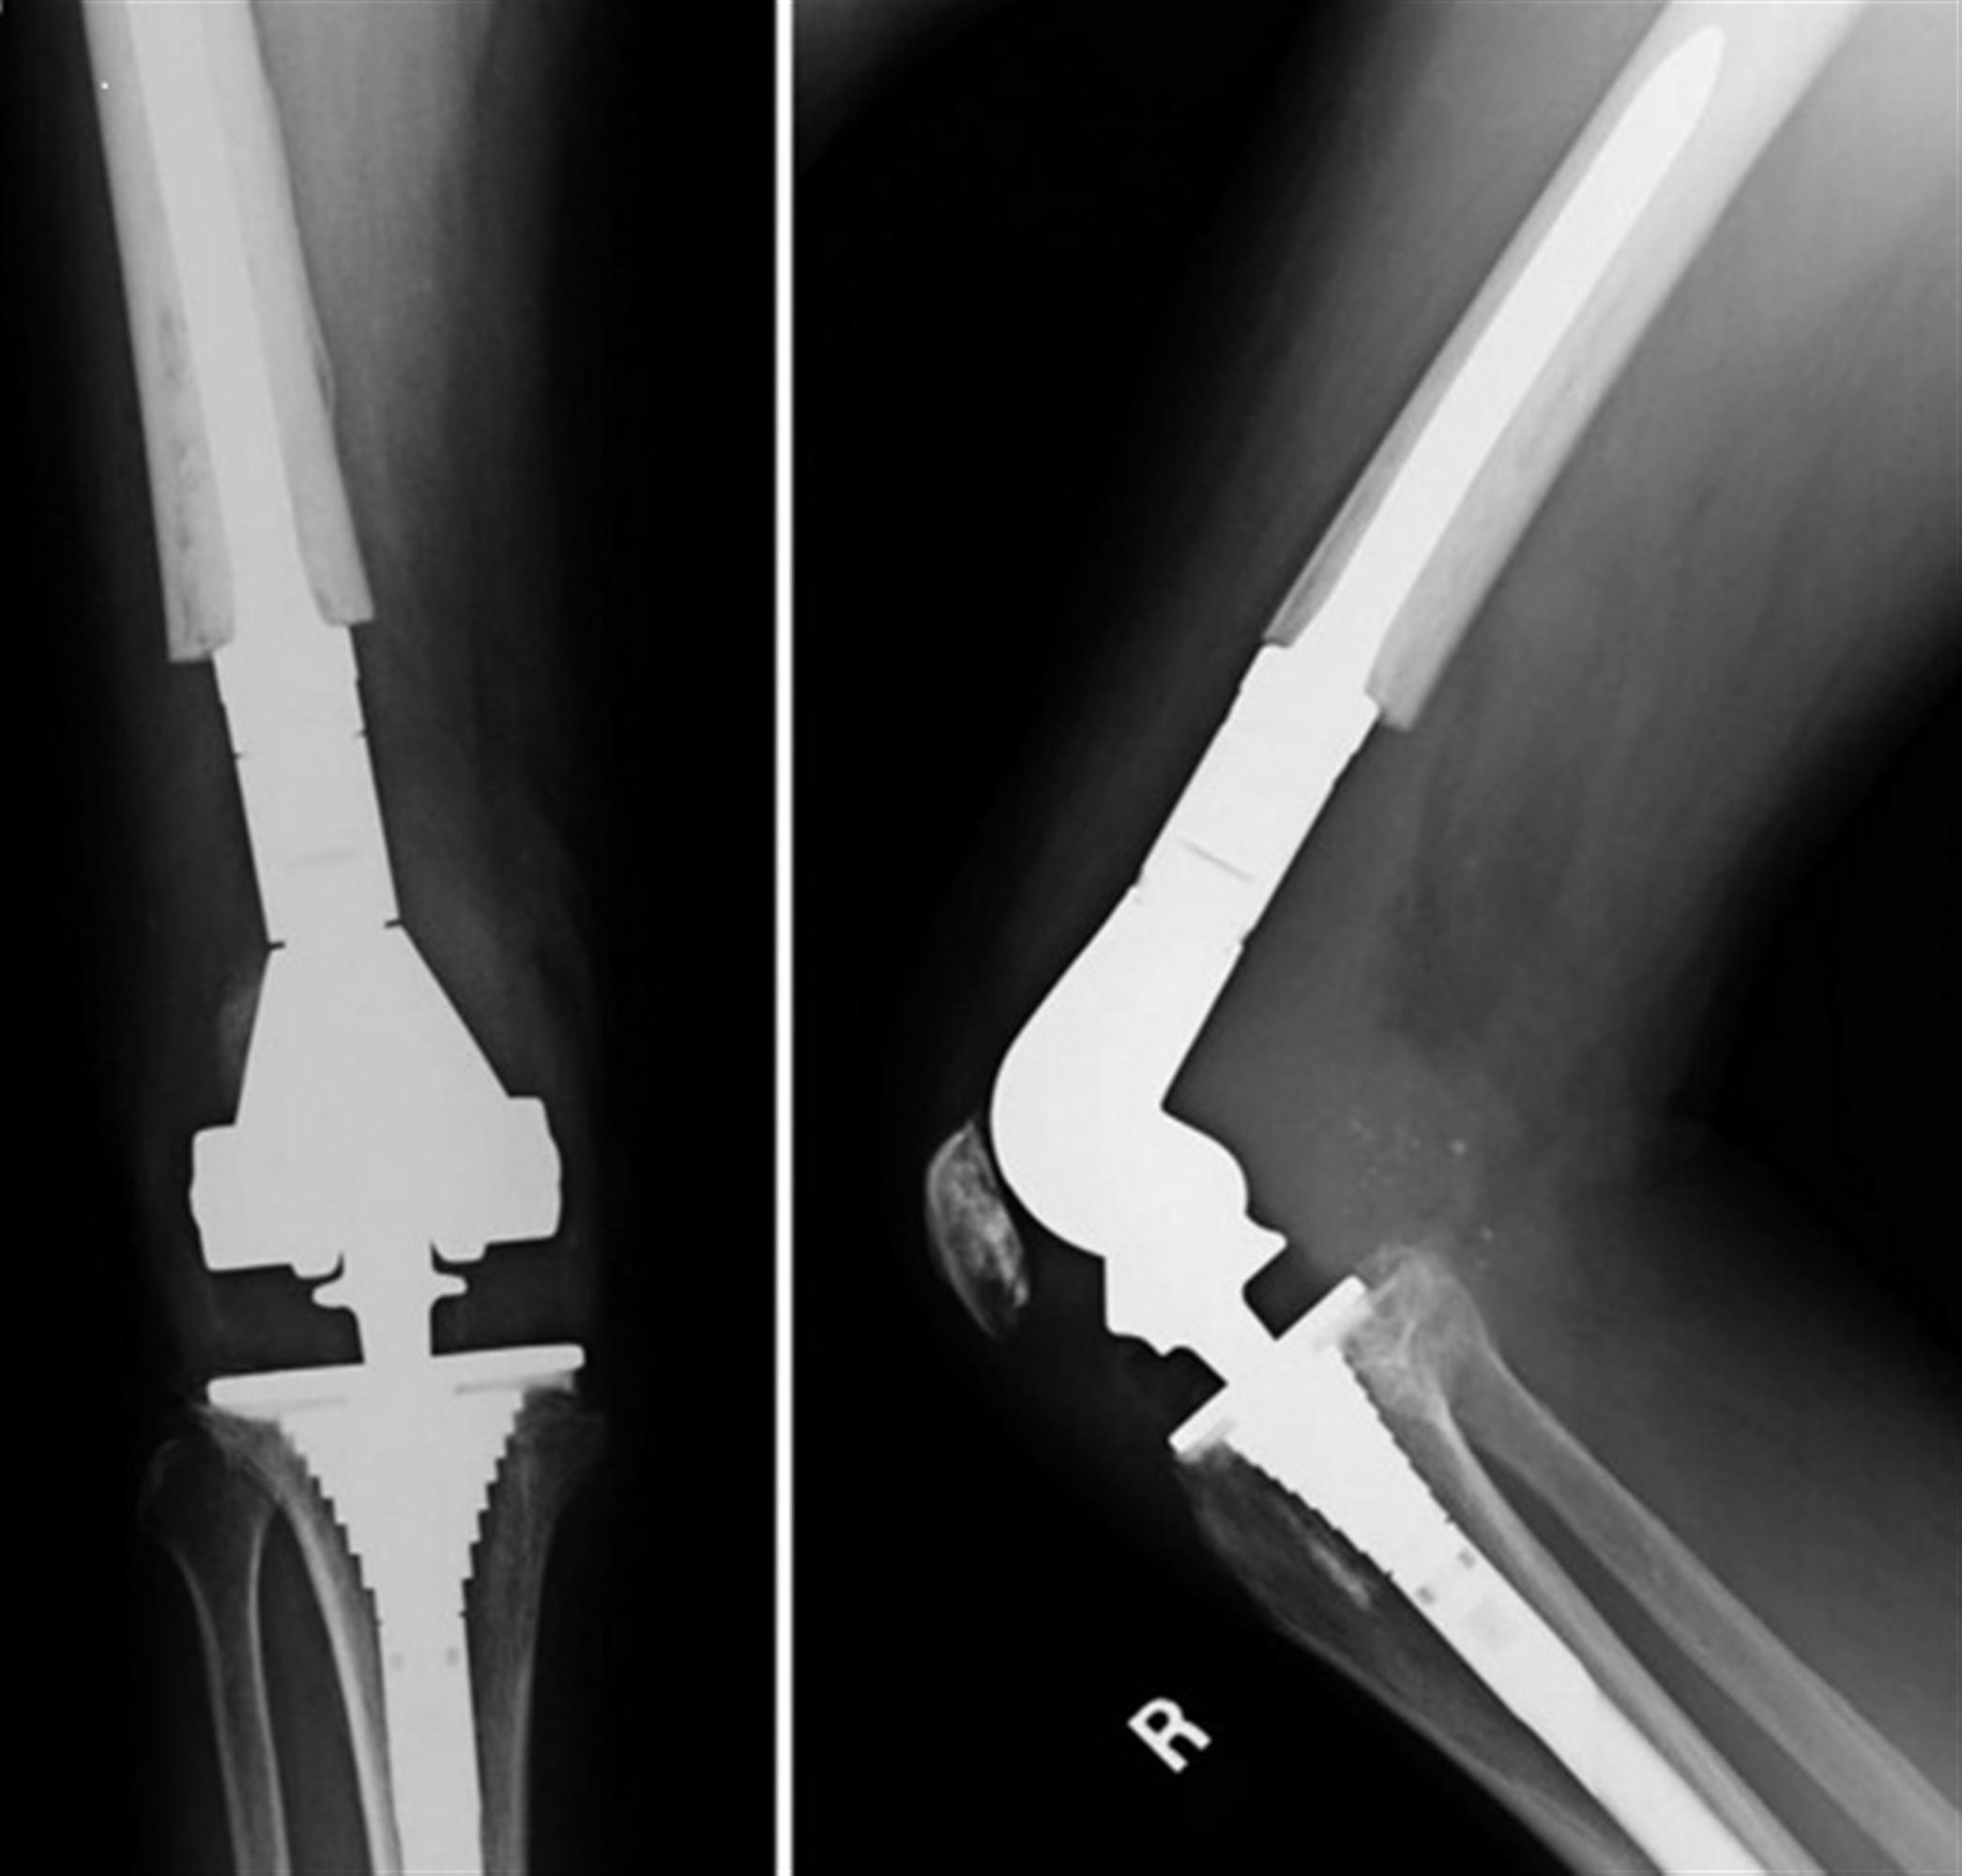

TKA Revision Recon Orthobullets

TKA Revision Recon Orthobullets Hinged Knee Orthobullets They are very useful in complex cases of total knee arthroplasty (tka). Hinged or highly constrained knee arthroplasty is a valuable treatment option for surgical salvage in situations where a sufficient. Learn about patella fracture, a traumatic knee injury that can affect the extensor mechanism. Guepar develops a new hinged prosthesis based on design by walldius that increases motion and. Hinged Knee Orthobullets.